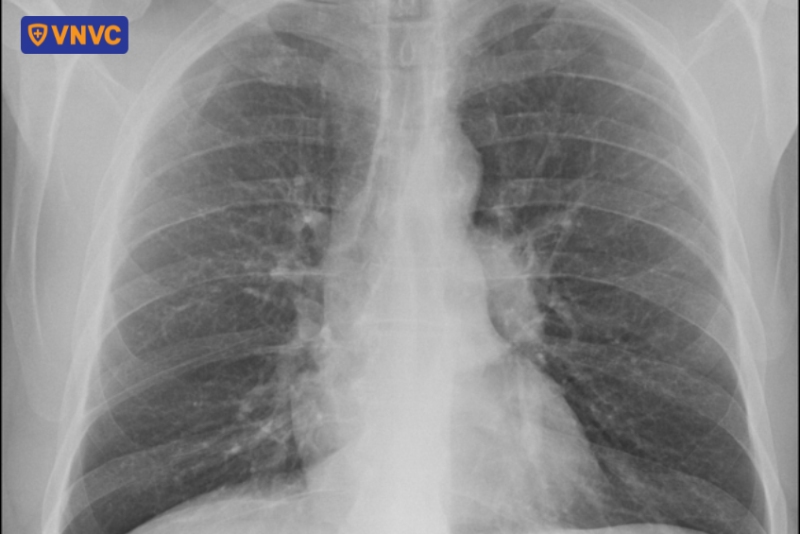

Bệnh Sarcoidosis (hay còn gọi là bệnh u hạt) do các u hạt nhỏ gây viêm trong phổi, có thể biểu hiện phì đại cân xứng của hạch bạch huyết quanh vùng rốn phổi và trung thất, tạo nên bóng đậm hai bên rốn phổi rõ rệt. Ngoài ra, phì đại hạch bạch huyết cũng có thể do nhiễm trùng (lao, nấm) hoặc các bệnh toàn thân khác gây ra, làm tăng kích thước và đậm độ rốn. (3)